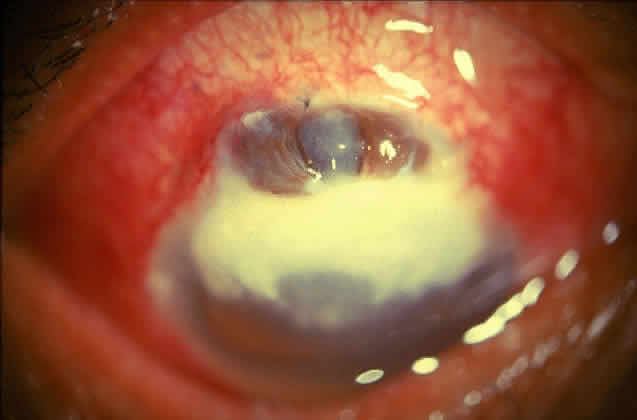

Bacterial corneal infections are caused by a wide variety of organisms. Pneumococcus seems to be the most common causative organism (Fig. 2); however, staphylococcal, pseudomonal, and gonococcal infections frequently are encountered.3 This may be related to chronic dacryocystitis.5

Fig. 2. Photograph demonstrating a pneumococcal corneal ulcer.